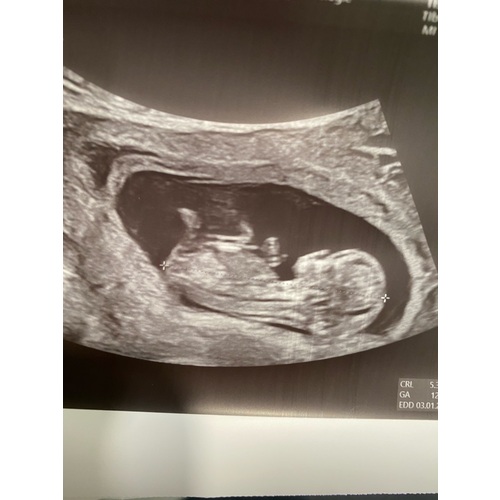

Met hoeveel weken is deze echo gemaakt?

12 weken

Ik denk toch ook dat het een jongetje is

Ik denk dat het de nub is, 12 weken is nog erg vroeg om nu al zo'n plasser te hebben 😅

Een vriendin van mij heeft met 13 weken een miskraam gehad. Het kindje is overleden met 11 weken en 6 dagen. Toen het kindje geboren werd kon je duidelijk zien dat het een jongetje was 🥰